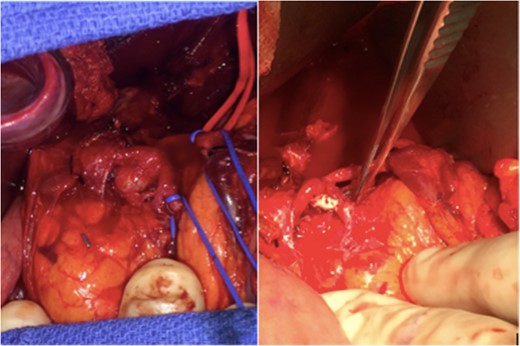

Intra-operative image demonstrating the anerusym in situ before repair (left) and the vascular patch repair following aneurysm removal (right). The pancreas is located inferior to the celiac artery in this image.